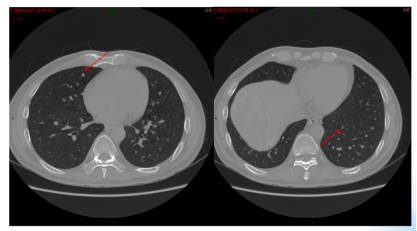

影像学检查:2024年7月30日,院外腹部CT显示乙状结肠管壁增厚,考虑肿瘤性病变(cT3N2,图1),2024年8月5日,肝脏MRI显示肝脏多发转移灶(侵犯门静脉右支、肝右静脉,图2)。2024年8月2日胸部CT显示双肺结节待排(图3)。

图2. 肝脏MRI

病情评估:基线评估肿瘤负荷大,肝脏多发转移(S2、S4肝脏弥漫性肿块),双肺结节待排。